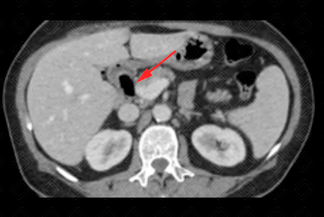

Texto alternativo para a imagem Figuras 1, 2, 3 e 4. Créditos: Dra. Elazir Mota - Rio de Janeiro/RJ.

Descrição das figuras 1, 2, 3 e 4: Tomografia computadorizada do abdome. Estudo pós-contraste (fase portal), cortes axiais e coronais evidenciando a presença de gás (setas vermelhas) no interior do colédoco e via biliar intra-hepática esquerda. Após colher nova história com a paciente, havia relato de procedimento recente (colangiopancreatografia retrógrada endoscópica [CPRE]).

Aerobilia: Também chamada de pneumobilia. Trata-se da presença de gás no interior da árvore biliar. As principais etiologias são abordagem recente das vias biliares (CPRE, colangiografia intra-operatória), incompetência do esfíncter de Oddi (congênita, uso de atropina, esfincterotomia e pancreatite crônica), fístula bilioentérica, processos infecciosos (colangite, colecistite enfisematosa, abscesso hepático e ruptura de cisto hidático).